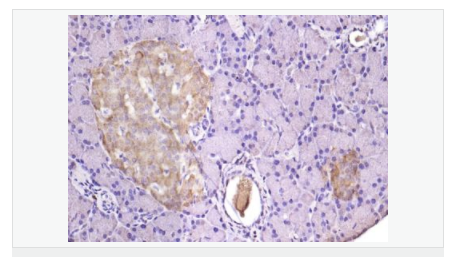

| 產(chǎn)品應(yīng)用 | WB=1:500-2000 ELISA=1:5000-10000 IHC-P=1:100-500 IHC-F=1:100-500 IF=1:100-500 (石蠟切片需做抗原修復(fù)) not yet tested in other applications. optimal dilutions/concentrations should be determined by the end user. |

| 細胞定位 | 細胞漿 細胞膜 |